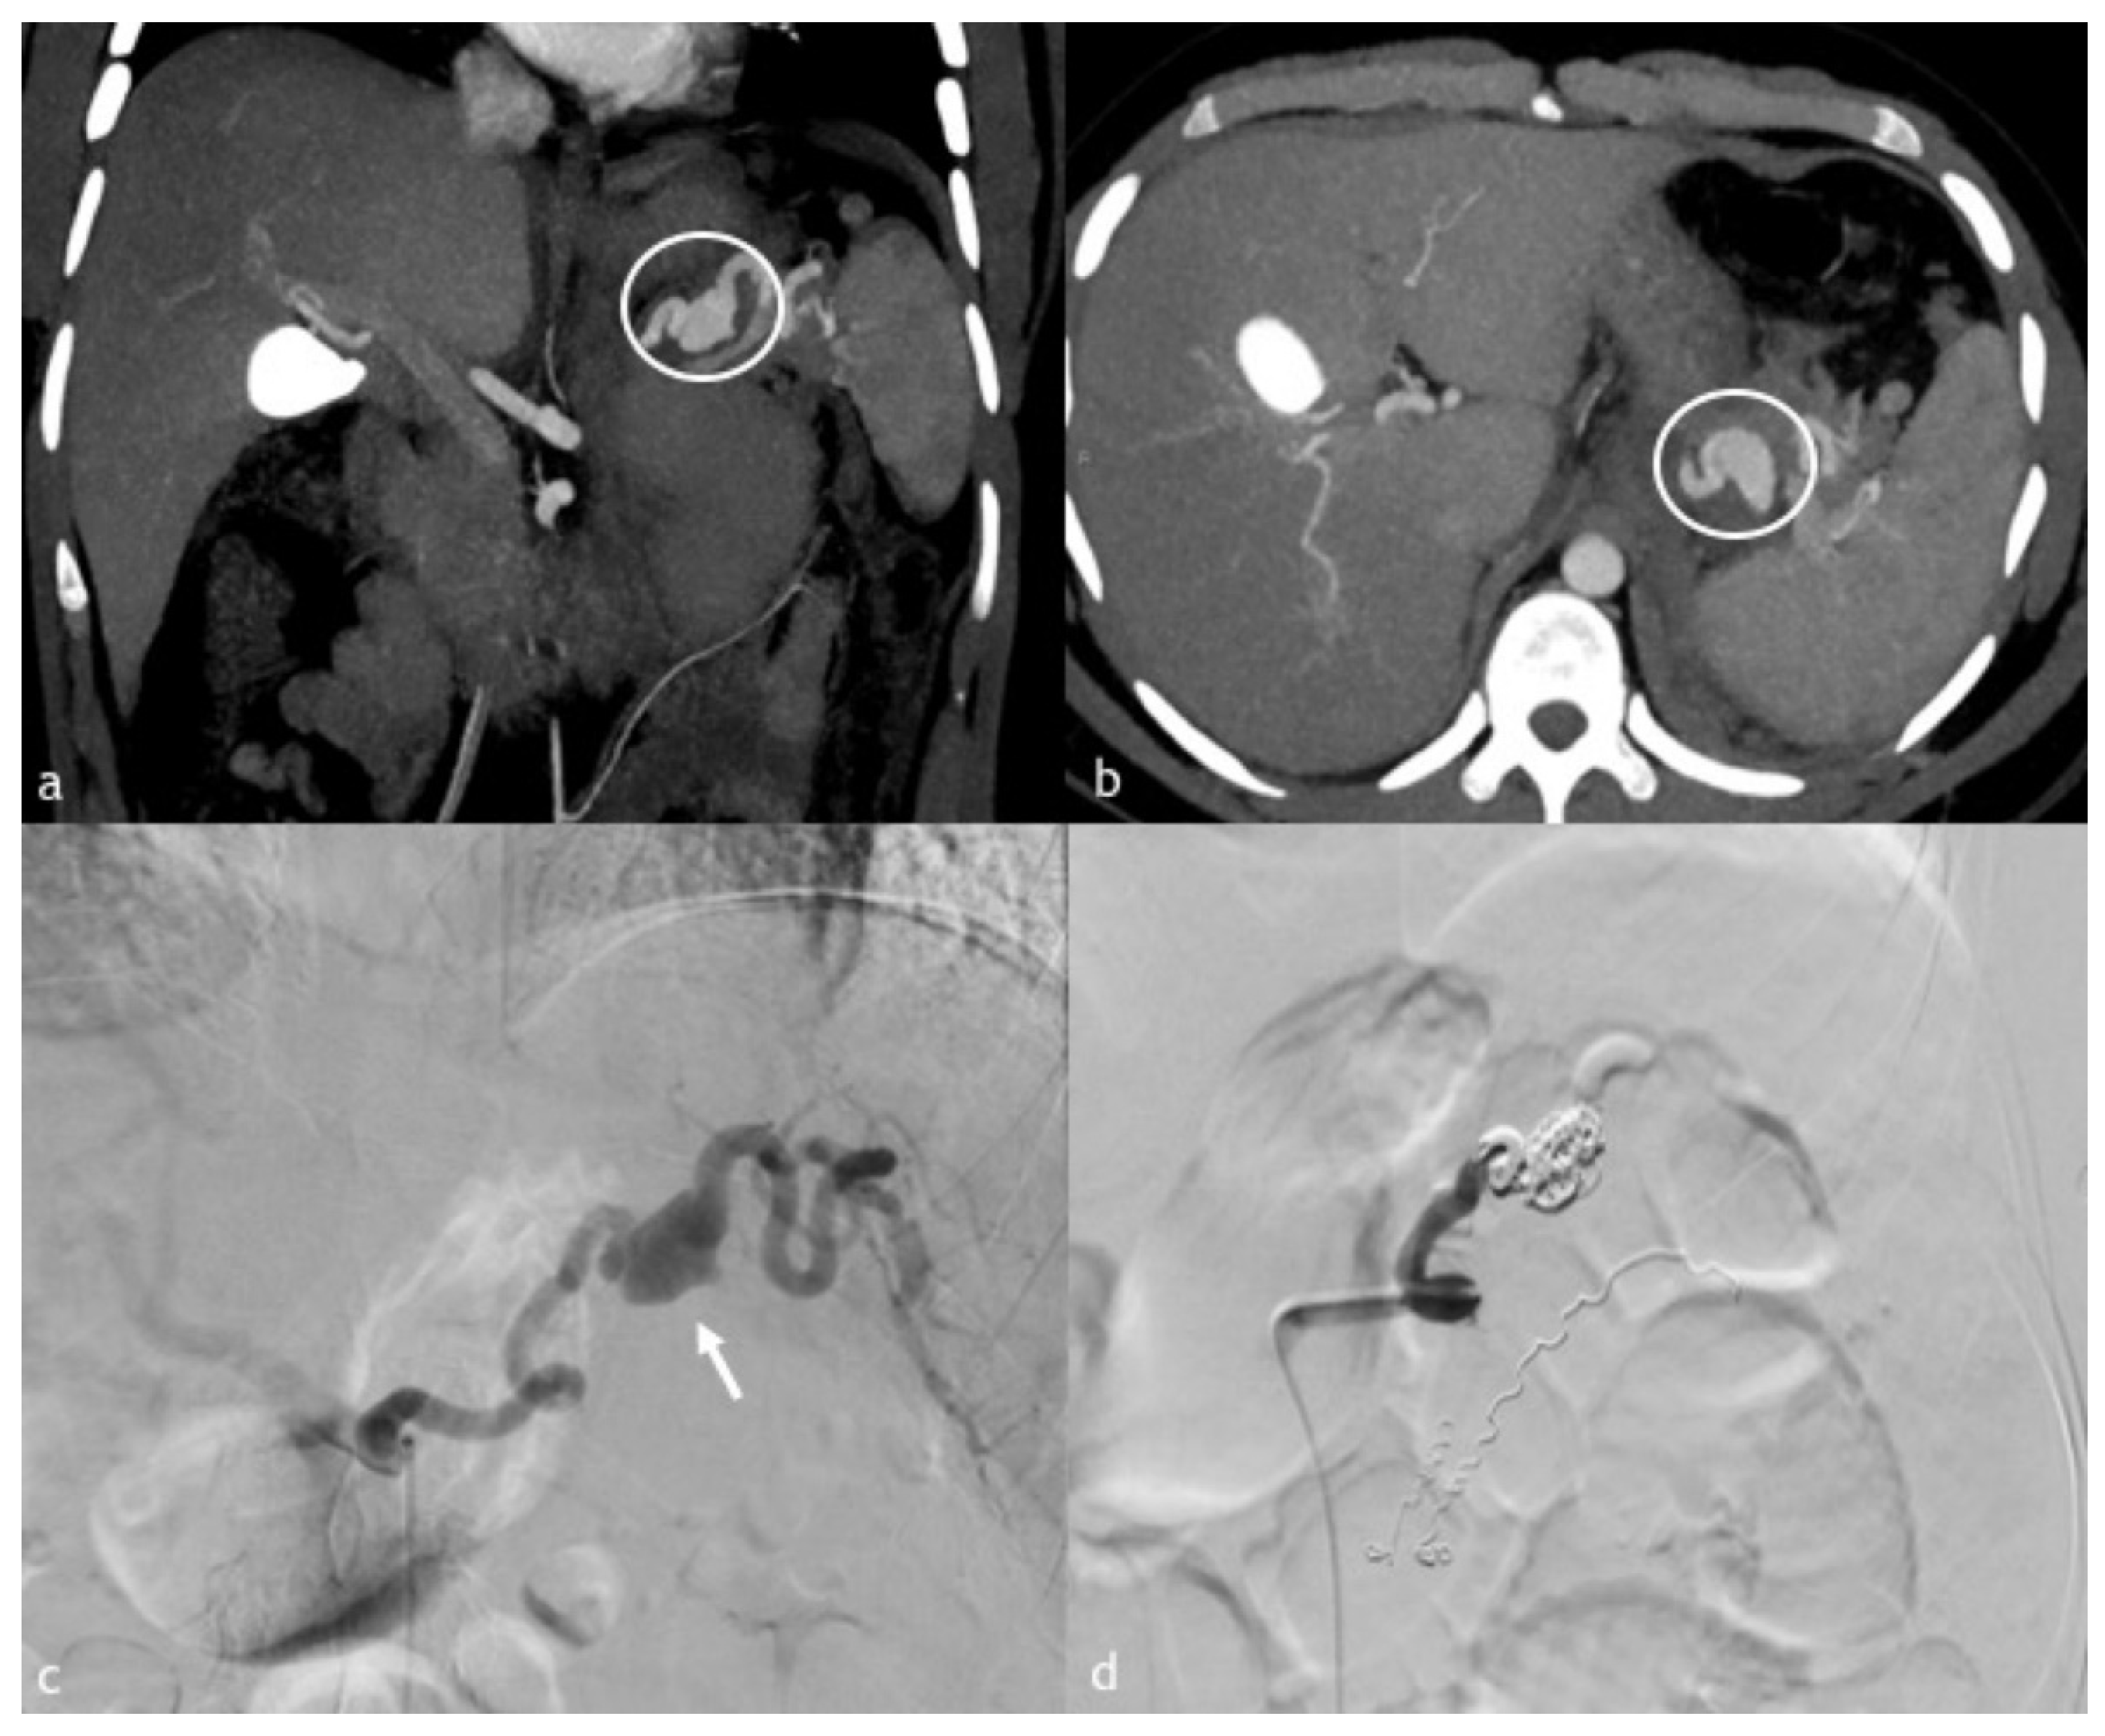

Figure 3. (ad). A 45-year-old woman presented a massive hematemesis after gastroentero-anastomosis due to ingestion of caustics. (a,b) Coronal and axial MPR reconstruction images demonstrate a spastic splenic artery with PSA formation directly bleeding in the stomach (circle). (c) Digital subtraction angiographic image shows splenic artery PSA rupture with massive bleeding in the stomach. (d) Post-embolization angiographic control shows complete occlusion of the splenic artery obtained with 1:1 mixture Glue/Lipiodol.